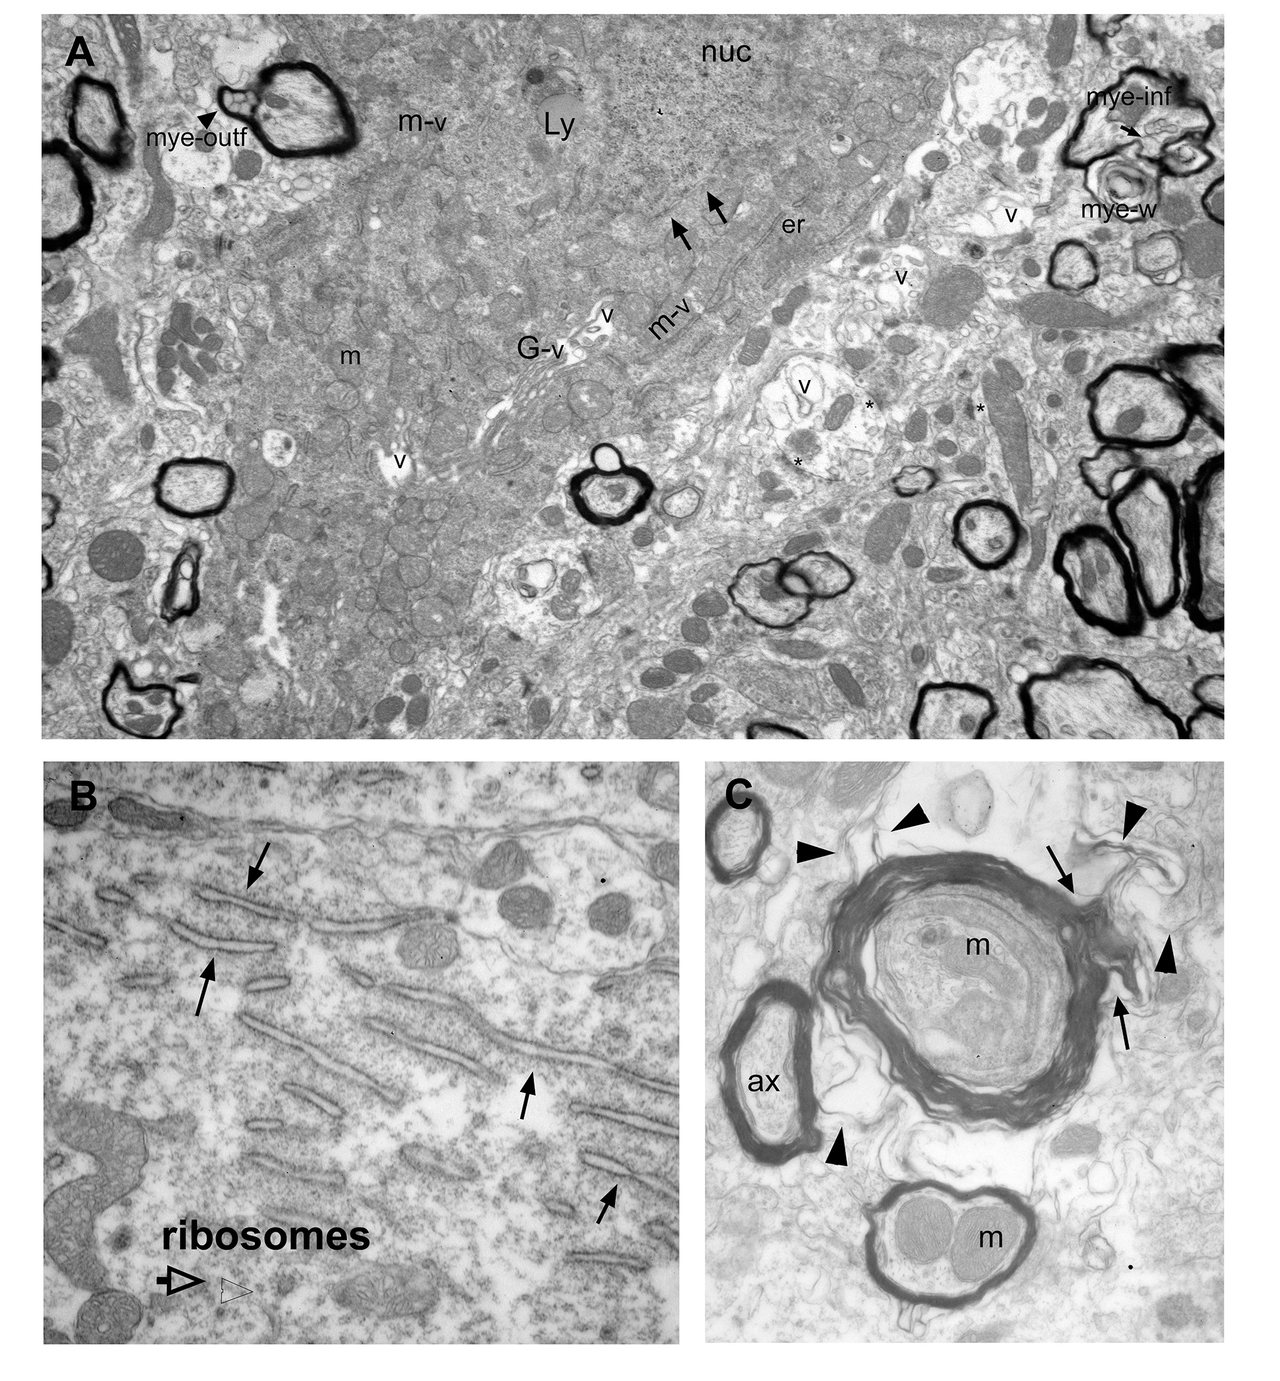

A. A large cell body cross-section, including a dendrite emergence point. Cytoplasm of this cell is not electron dense however, many degeneration products fill the cell, scattered among discernable mitochondria (m).

B, C and D are enlarged views of the regions in A, marked with orange, green and purple frames.